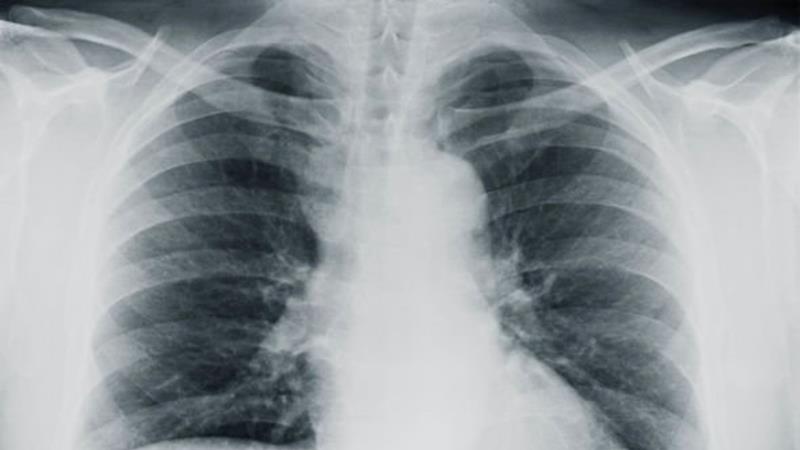

ด้านศูนย์ควบคุมและป้องกันโรคจีนเปิดเผยว่า ได้ตรวจสอบผู้ที่เข้าข่ายอาจได้รับเชื้อจากผู้ป่วยทั้งสองราย รวมถึงโรงพยาบาลแล้ว และได้เพิ่มการสอดส่องหาผู้ที่มีอาการคล้ายกัน ทั้งนี้กาฬโรคปอดเป็นโรคที่มีหนูเป็นพาหะ และมีอัตราการเสียชีวิตในมนุษย์ถึงเกือบ 100 เปอร์เซ็นต์ หากไม่ได้รับการรักษา